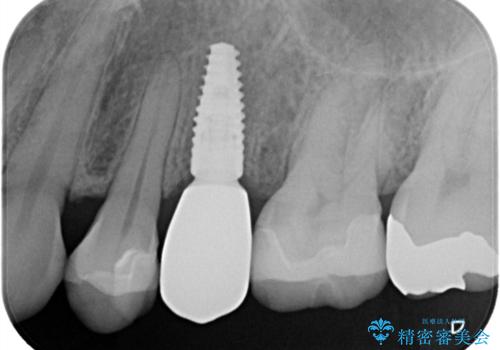

歯が割れてしまった インプラント治療で噛めるように!

- 根管治療をしている歯が破折し、抜歯となってしまいました。

抜歯した部位に対して、はじめに可撤性部分義歯,ブリッジ、インプラントによる治療方法とそれぞれの利点と欠点について説明を行った結果、インプラント治療を希望されました。さらに、インプラント治療の術前・術後口腔内管理の重要性、手術内容,費用などを説明し、十分なインフォームド・コンセントを得たうえで治療を開始しました。

今回の症例では、骨の量が十分あったため、比較的短期間で治療を完了することができました。インプラントを使用することで、安定した咬み合わせが実現し、患者様は痛みもなく安心して食事を楽しむことができるようになりました。